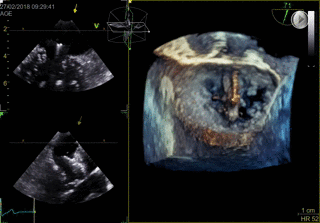

LAAC

- Roy, et al. Novel Integrated 3D Multi-Detector Computed Tomography and Fluoroscopy Fusion for Left Atrial Appendage Occlusion Procedures. Catheter Cardiovasc Interv 2017;Mar 17, DOI:10.1002/ccd.26998